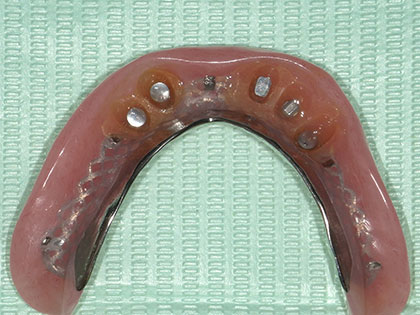

• 義歯(入れ歯)治療中1

• 義歯(入れ歯)治療中2

• 義歯(入れ歯)治療中3